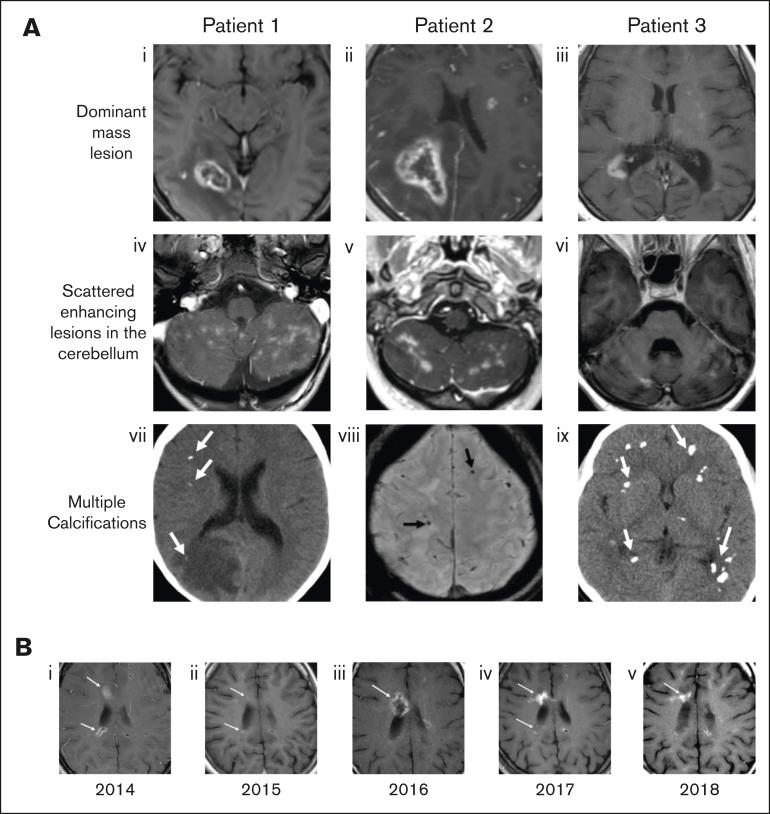

Fanconi anemia (FA) is a complex inherited bone marrow failure syndrome characterized by chromosomal instability and defective DNA repair, causing sensitivity to DNA interstrand crosslinking agents. Our understanding of the full adult phenotype of the disease continues to evolve, because most patients with FA died of marrow failure in the first decade of life before more recent advances in allogeneic hematopoietic cell transplantation. Herein, we report a previously undescribed, clinically concerning, progressive neurologic syndrome in patients with FA. Nine nonimmunosuppressed pediatric patients and young adults with FA presented with acute and chronic neurological signs and symptoms associated with distinct neuroradiological findings. Symptoms included, but were not limited to, limb weakness, papilledema, gait abnormalities, headaches, dysphagia, visual changes, and seizures. Brain imaging demonstrated a characteristic radiographic appearance of numerous cerebral and cerebellar lesions with associated calcifications and often a dominant ring-enhancing lesion. Tissue from the dominant brain lesions in 4 patients showed nonspecific atypical glial proliferation, and a small number of polyomavirus-infected microglial cells were identified by immunohistochemistry in 2 patients. Numerous interventions were pursued across this cohort, in general with no improvement. Overall, these patients demonstrated significant progressive neurologic decline. This cohort highlights the importance of recognizing FA neuroinflammatory syndrome, which is distinct from malignancy, and warrants careful ongoing evaluation by clinicians.